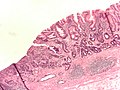

Microscopic

Features - variable, either of the two following:

- "Typical adenocarcinoma":

- Gland-forming lesion that infiltrates into the lamina propria or beyond.

- Nuclear pleomorphism - common.

- +/-Signet ring carcinoma.

- Scattered single cells in the lamina propria or beyond with:

- Abundant cytoplasm containing one large (mucin-filled) vacuole.

- A peripheral nucleus (displaced by the vacuole).